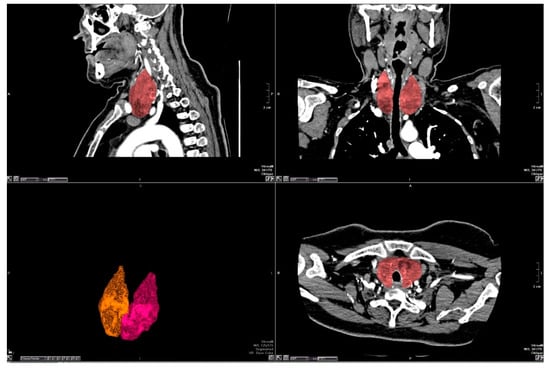

2.2.2. Image Evaluation